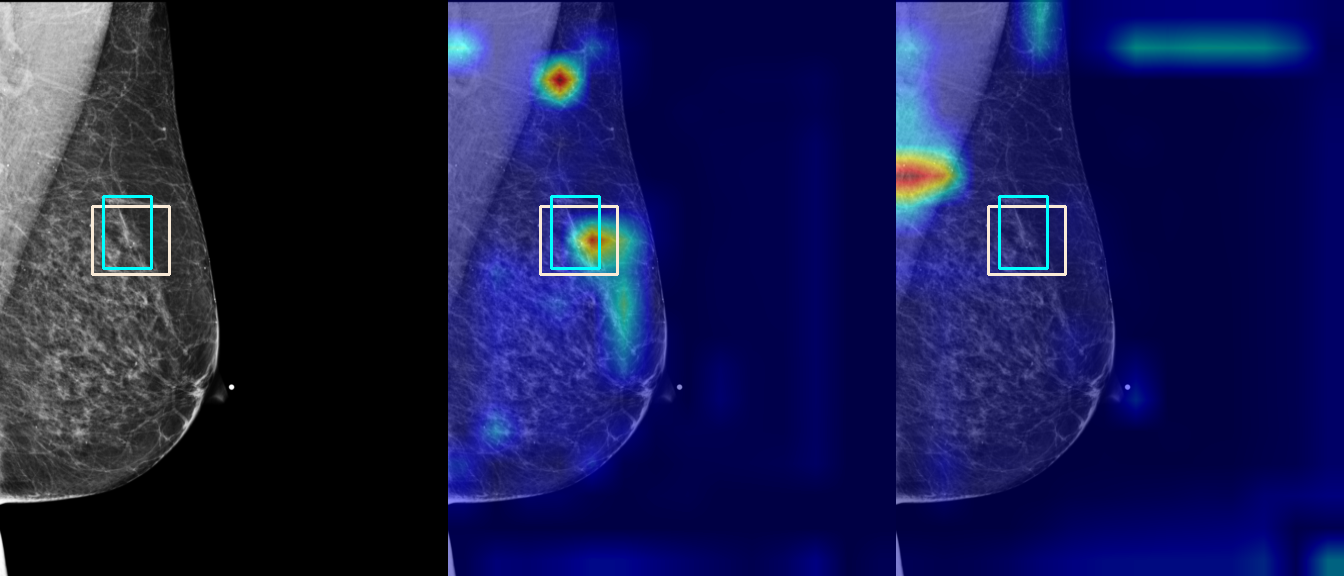

To interpret the decision-making process behind the quantitative results, we visualized Class Activation Maps (CAM) for the top-performing methods, ERM and VREx. Figures 1 through 2 illustrate discriminative regions identified by the models within the full mammograms.

Localization of Clinical Features: A key concern in medical AI is whether high performance stems from genuine pathology detection or spurious background correlations. Our visualizations suggest that Standard ERM achieves its superior quantitative performance by predominantly prioritizing clinical cues. As shown in the top rows of the Figure 1 and Figure 2, the ERM-trained models consistently focus attention on the specific lesion regions within the breast tissue. This demonstrates that despite lacking explicit invariance constraints, ERM is capable of learning robust, medically relevant features when trained on diverse multi-source data.

Attention Drift in Both Methods: While both ERM and VREx generally identify the correct region of interest in successful cases, neither method is immune to attention drift. We observe instances in both training paradigms where the model focuses on irrelevant areas, such as healthy fibroglandular tissue or background artifacts (e.g., rows 5 and 6 in Figure 1). This indicates that while VREx is designed to penalize instability, it does not guarantee perfect anatomical focus compared to the unconstrained ERM baseline.